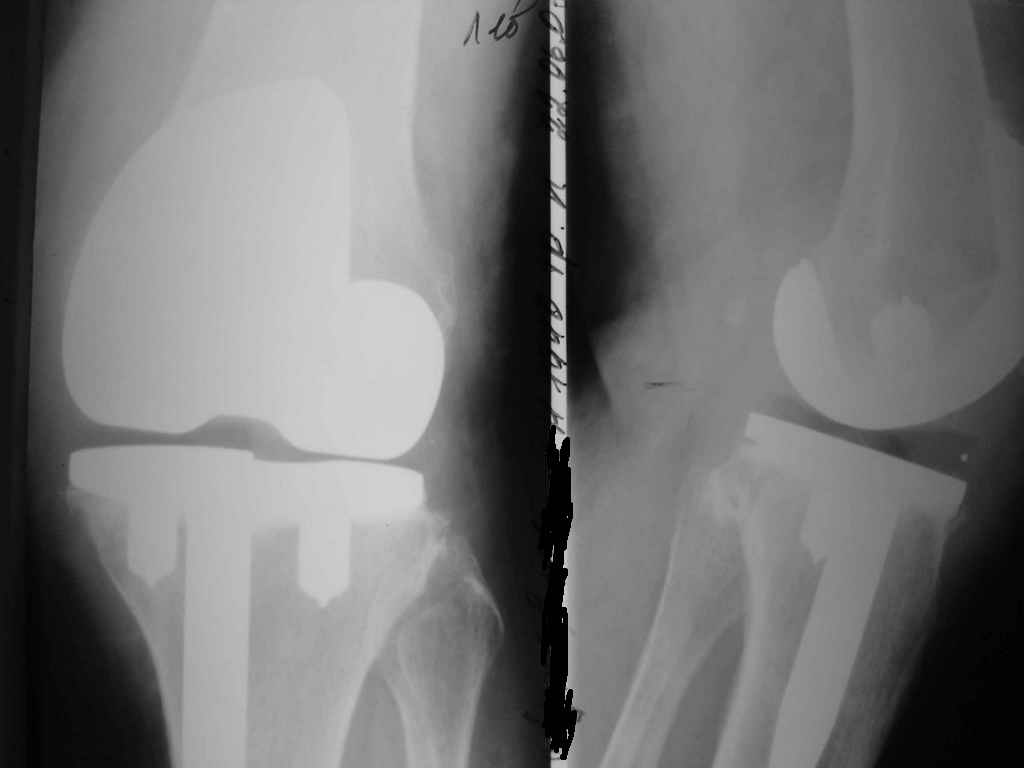

Уважаемые коллеги. Пациентка 65 лет соматически сохранна 6,5 месяцев назад выполнено замещение

коленного сустава интегральным эндопротезом Фримана Самуэльссона - цемент, по поводу ДОА.

Послеоперационное течение с длительным субфебрилитетом. Местно без особенностей и выписана домой на 28 сутки с обьемом движений в колене 90 град. с частичной опорой. Дома отмечала субфебрильную лихорадку. Живет в небольшом поселке далеко от цивилизации. Контрольный осмотр в 3 месяца особых клинических проблем лечащий врач не нашел. Однако рентгенологически отмечены зоны остеопороза вокруг компонентов, на которые не обратил внимание. С 4 месяца отметила ухудшение - отек в колене, ограничение движений и боль. Лечилась у местного врача-хирурга (нестероиды и местно мазилки) - без эффекта. Обратилась только в 6,5 мес. Движения в суставе 20 град, отечность колена, выпот по УЗИ. Боль неопределенная, ходит с тростью. Лихорадки нет, в ан крови СОЭ 36 остальное норма, острофазовые тесты СРР повышен вдвое = 12 (при норме 6) Ревмотест - норма..

Пункция - посев - роста не дает. Пробовали артроскопию - артрофиброз. Трудности осмотра из-за

контрактуры и спаек. Рентгенограммы в динамике - в приложении (динамика с ухудшением). Вопросы:

1. Инфекция? или остеопения местная?

2. Ревизия или подождать и полечить остеотропами?